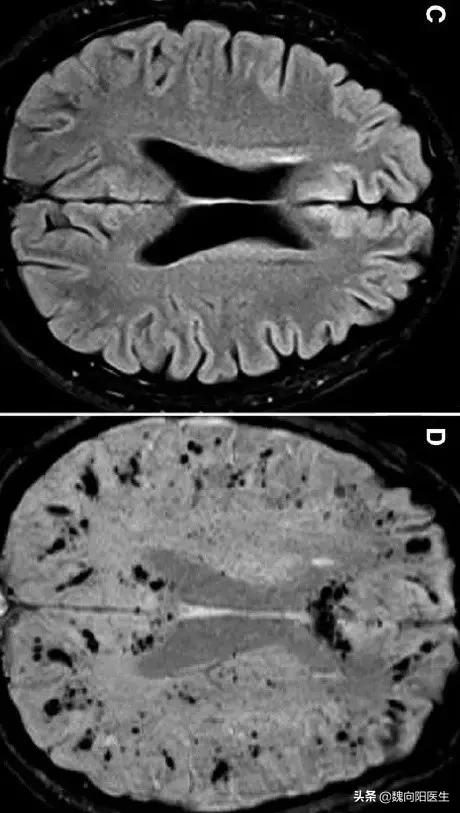

脑小血管病是指各种病因影响脑内小动脉、微动脉、毛细血管、微静脉和小静脉所导致的一系列临床、影像学和病理综合征。

- 单一小动脉(小血管)的阻塞会导致散在的腔隙性梗死,皮层下白质易受损。

- 由于小动脉狭窄和低灌注同时影响了多支血管,导致两个或多个动脉的边缘带缺血,侧脑室旁和深部白质受损害。

腔隙性梗死或深部白质病变破坏了额叶(顶叶)-皮层下通路,导致认知功能损害发生,甚至加重至痴呆。